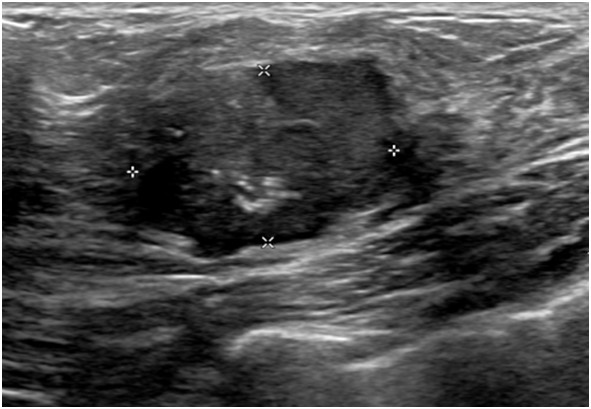

常珮雲說,乳房超音波可發現許多良性的病兆,例如纖維腺瘤、纖維囊腫、脂肪瘤、淋巴結腫大、鈣化、隆乳的植入物是否滲漏或術後導致的乳房結構異常等。且因乳房超音波沒有輻射,因此某些族群非常適合做這項檢查,簡述如下:

2.超音波適用於年輕女性,因為年輕女性乳腺較緻密發達,若用於乳房攝影時影像上緻密的乳腺及病灶顏色會相近,較難以區分判讀;但若於超音波有發現病灶且須進一步追蹤時,還是需要加照乳房攝影做參考比對。

4.但因超音波無法發現微小鈣化點,也無法提供全幅的乳房影像,所以有時會同時利用乳房超音波與乳房X光攝影進行檢查,可以互補彼此之不足,是最安全的做法。